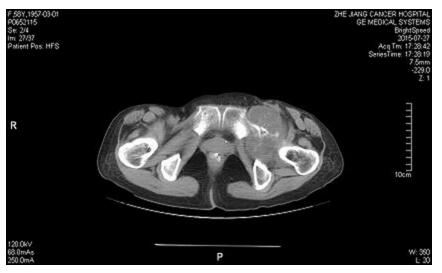

根据CT可见肿瘤累犯髋臼、耻骨下支、坐骨及部分髂骨,结合术前穿刺病理考虑软骨肉瘤,软骨肉瘤放化疗不敏感,手术为唯一根治性治疗手段,但耻骨上支后方闭孔动静脉与髂外或腹壁下动静脉会存在异常的吻合支,被称为“死亡之冠”,一旦不小心切断,很难实现止血,但是巨大的肿瘤往往遮挡手术的操作空间,很难有足够清晰的视野暴露血管,稍有不慎就将带来汹涌的出血并会危及生命。李涛主任带领整个团队经过术前反复讨论、缜密设计和充分准备,给病人实行了左骨盆肿瘤切除+全髋置换+髋臼修复+骨盆生物力学重建术,该术式利用自身骨质重建骨盆环,具有骨性愈合的特点,可以有效避免目前流行的单纯骨盆假体置换造成假体松动,脱位从而导致手术失败的缺点。